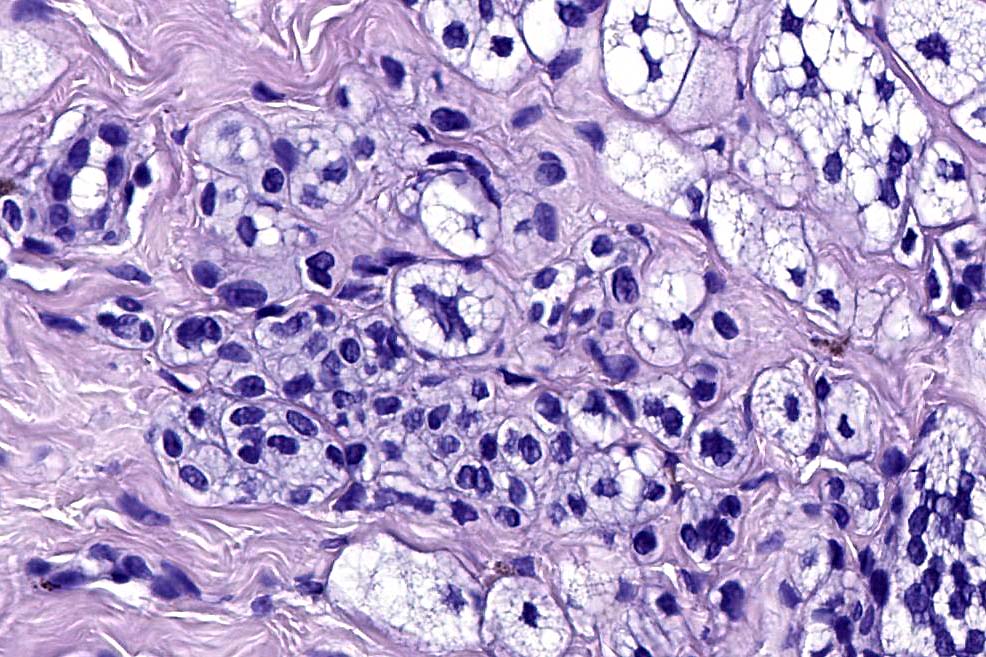

.Balloon cell change is most often seen in banal melanocytic nevi but it has also rarely been described in cellular blue nevus, dysplastic nevus, combined nevus, halo nevus & Spitz nevus. Lesions with <50% of balloon cells are sometimes described as nevi with balloon cells. Nevi with >50% balloon cells are described as balloon cell nevus.

.Balloon cell nevs genrally has uniform, hyperchromatic nuceli (as opposed to the vesicular nuclei with prominent nucleoli) seen in melanoma. Mitoses are absent.(In my experience, balloon cell melanoma is more common than balloon cell nevus).

The importance of the entity is that it must always be distinguished from balloon cell melanoma. All cases should be scrutinized very carefully for pleomorphism and mitotic activiy before rendering a diagnosis of balloon cell nevus.